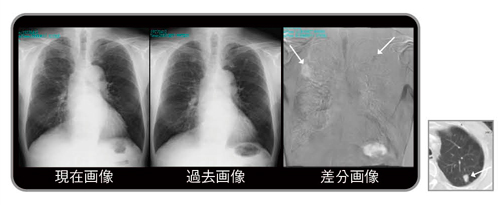

1980年代に商品化されたデジタル画像は,その後急速に普及し,2010年代の今ではほとんどの医療用画像はデジタル化され,モニタにより診断や治療が行われている1)。本稿で紹介する経時的差分法(temporal subtraction:TS)は,現在画像から過去画像を自動的に引き算して,変化のあった病変のみを強調して表示する手法で,新しく出現した病変を黒く表示し,消失した病変は白く表示させることで読影を支援するシステムである(図1)。

図1 差分画像の見え方

左上肺野の小結節出現(黒く表示),右中肺野の肺炎消失(白く表示)

従来の比較読影に,さらに差分画像を追加することにより,正常肺構造や既存肺病変に隠れがちな新規病変は,病変のみが明瞭に描出されるようになるため,読影時の気づきに大きな貢献が期待できる。また,従来の読影法のように一か所ごとに病変を見比べるのではなく,差分画像を一瞥するだけで胸部全体の変化のある病変だけを把握でき,読影時間の短縮につながることが期待できる。